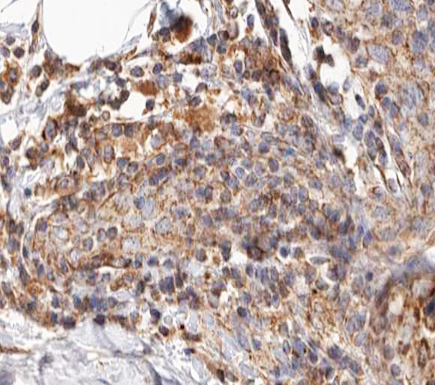

- Main image

- Experimental details

- 1:100 staining human breast carcinoma tissue by IHC-P. The tissue was formaldehyde fixed and a heat mediated antigen retrieval step in citrate buffer was performed. The tissue was then blocked and incubated with the antibody for 1.5 hours at 22°C. An HRP conjugated goat anti-rabbit antibody was used as the secondary.